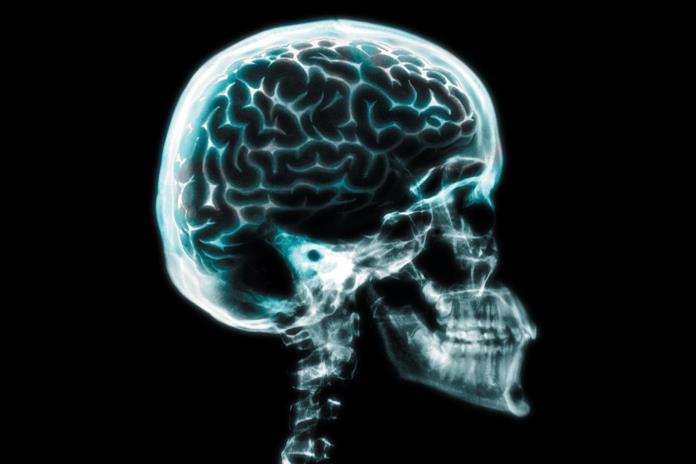

Importantes investigaciones relacionadas con el cerebro se darán a conocer en el Encuentro Anual Neurociencias, estudios como las emociones en la adolescencia, el trastorno limítrofe de la personalidad que afecta a las mujeres, el trastorno con déficit de atención con hiperactividad, epilepsia, esquizofrenia y el leguaje en personas sordas.

La investigadora del Instituto de Neurociencias del CUCBA, Julieta Ramos expuso que otras investigaciones sobresale la técnica para la percepción de los sonidos en la población sorda.

Además la doctora Julieta Ramos dará a conocer los resultados de la investigación sobre el cerebro emocional y el estrés y los trastornos de personalidad que ocasiona.